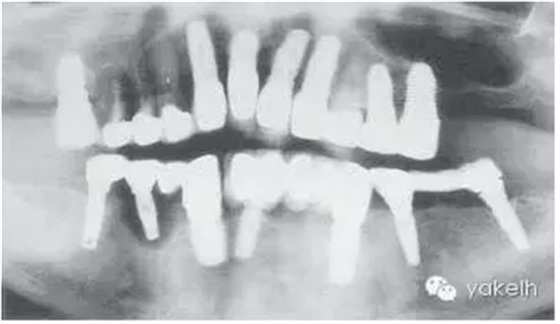

病例9

這個(gè)病例使用種植修復(fù),效果較差。在上頜前牙區(qū),存在嚴(yán)重的美學(xué)問題(圖.12A)。

下頜有一顆種植體位于LR1和LR2之間的外展隙區(qū)域,這不僅影響美觀,同時(shí)也不利于口腔衛(wèi)生的維護(hù)(圖.12B)。

大多數(shù)修復(fù)體都發(fā)生了崩瓷,治療效果不佳(圖.12C)。LR5種植體周圍溢膿,存在種植體周圍炎(圖.12D)。

該病例全頜曲面斷層片顯示(圖.13)種植體修復(fù)存在一系列問題。LR5種植體周圍骨組織完全喪失,LL3發(fā)生了種植體周圍炎,LL6冠與基臺(tái)未完全密合。

圖.12 該病例臨床效果差。多個(gè)修復(fù)體失敗,發(fā)生了種植體周圍炎,還存在美學(xué)問題。

圖13 全頜曲面斷層片進(jìn)一步證實(shí)LR5種植失敗,其他種植體存在種植體周圍炎以及修復(fù)體與基臺(tái)不密合。